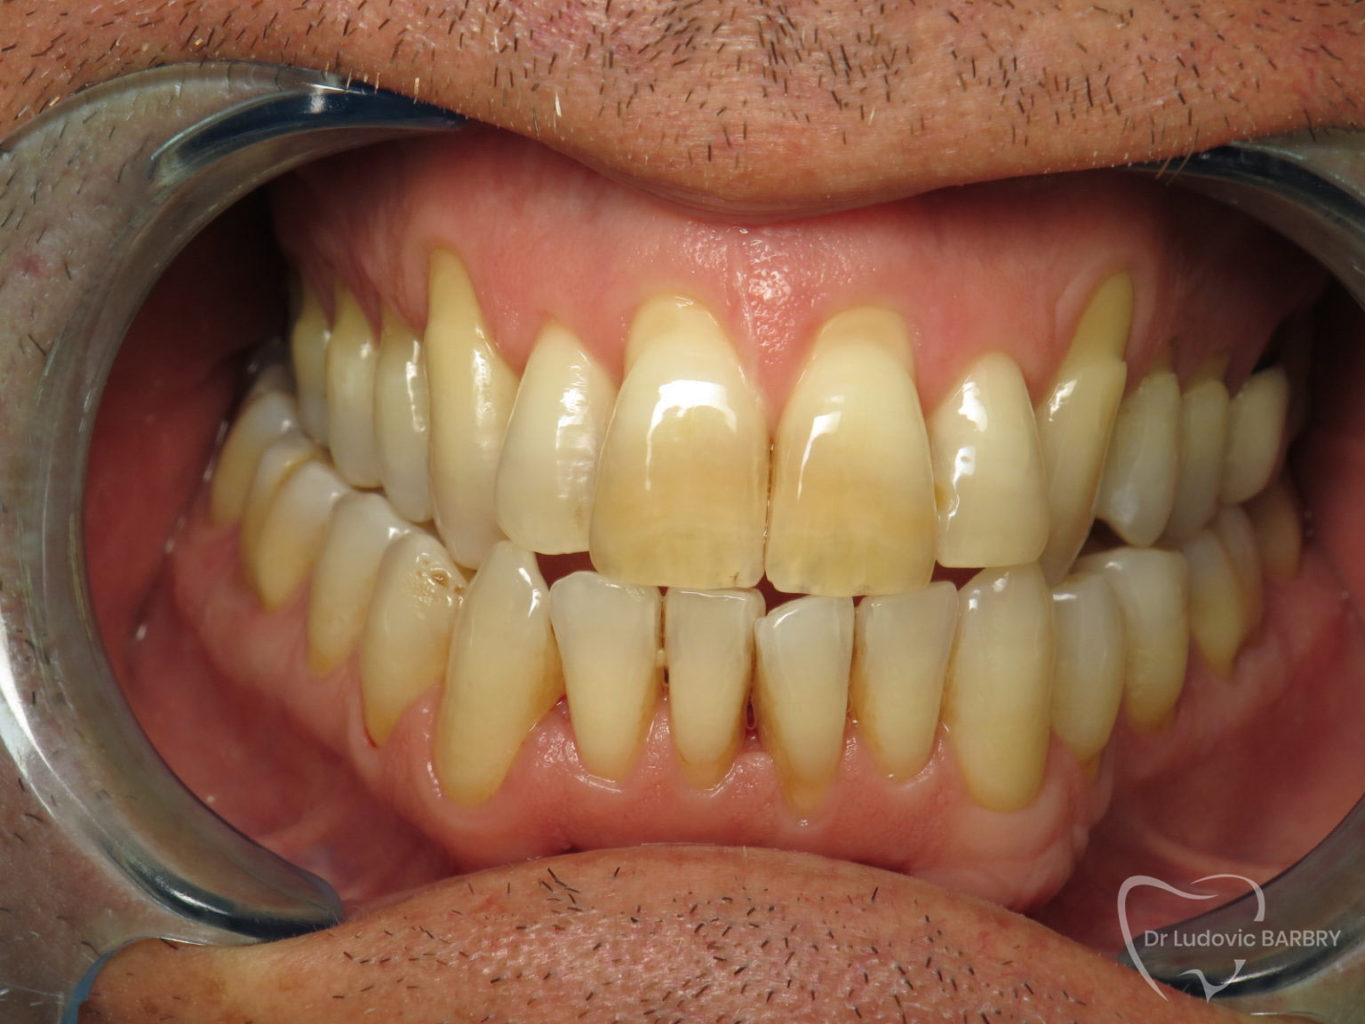

avant traitement

fin de traitement paro